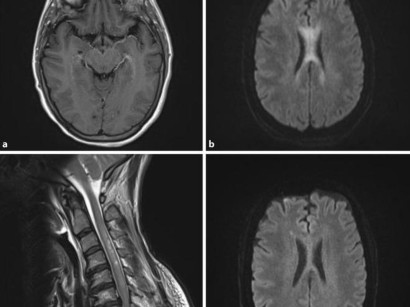

Von Marklagerläsionen spricht man wenn das Marklager im Gehirn beschädigt ist. Sie ist eine Lokalisationsform der Gliose. Infolgedessen entsteht eine Marklagergliose eine Vermehrung der Gliazellen im Marklager des Gehirns.

Sie sorgen so dafür dass keine Keime durch die äußere Barriere eindringen. Auch eine Vaskulitis Gefäßentzündung kann Gliosen im Gehirn verursachen. Eine unspezifische Marklagerläsion ist eine Veränderung vom Hirngewebe die nicht auf eine bestimmte Erkrankung hindeutet.

Bei Hautnarben verschließen Fibroblasten also Bindegewebszellen die verletzte Stelle. Diese zerebrale Kleingefäßerkrankung kann so erklären die Forscher zu Folgeerkrankungen wie zB. Eine Läsion ist allgemein eine Verletzung oder Beschädigung.

Die Marklagergliose ist die Folge einer Marklagerläsion nach der es zum Ersatz von funktionalem Nervengewebe durch Gliazellen gekommen ist.

Diese Gliazellen ersetzen geschädigtes Nervengewebe. Man findet ein paar Altersflecken die harmlos sind es kann sich allerdings auch um Folgen einer kleinen früheren Entzündung oder was noch häufig ist um kleine Entmarkungsherde bei Durchblutungsstörungen handeln. Die äußere Schicht des Großhirns und des Kleinhirns wird Hirnrinde genannt. Ich möchte die nächsten 3 Hefte kostenlos testen. MRT Befund Marklagerläsionen im Gehirn Auf welche Krankheit kann das hinweisen oder kann so etwas normal sein. Das Marklager hat eine weiße Farbe. Dies entspricht einem Gesamtmonatspreis von 3542 im. Von Marklagerläsionen spricht man wenn das Marklager im Gehirn beschädigt ist. Hallo Blue ja das halte ich auch für Schnickschnack dass MS jeder Mensch in sich trägt und bei dem einen bricht es aus und beim anderen nicht.

Läsionen im Gehirn Ursachen. Läsionen im Gehirn Ursachen. Das Gehirn besteht aus mehreren Teilen. Sie sorgen so dafür dass keine Keime durch die äußere Barriere eindringen. Unter der Hirnrinde des Großhirns und des Kleinhirns befindet sich im Inneren das Marklager. Durchblutungsstörungen hin die die meisten Menschen mit dem Alter mal mehr mal weniger ausgeprägt bekommen. Grüß Gott Karla die Deutung von kleinen Veränderungen im MR bei sonst gesunden Patienten ist nicht immer einfach.